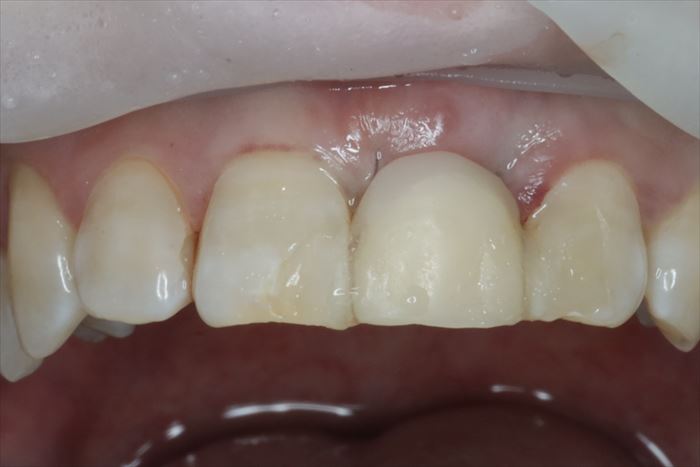

本日の抜歯即時インプラント埋入オペ終了時の写真です。

3ヶ月の治癒期間を取り、上部構造の製作に移ります。